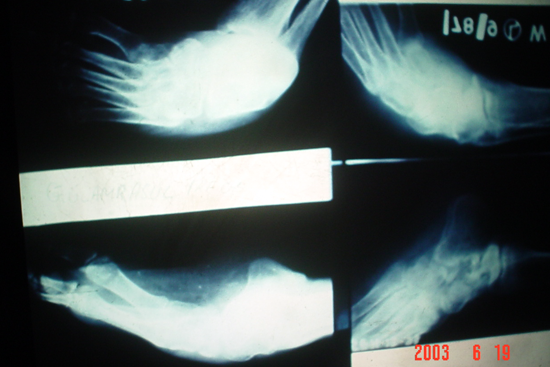

TEV

Aarti

Gulam Rasul